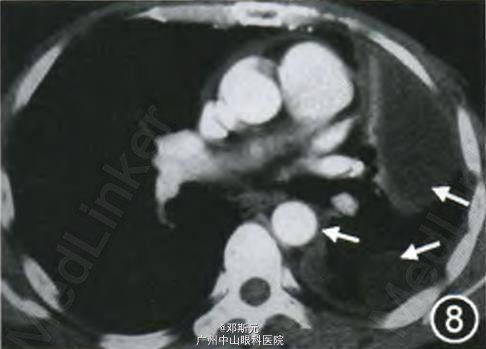

因患者左侧胸膜广泛增厚并左侧胸腔包裹性积液,左侧胸廓塌陷,手术完整切除困难,患者于2013年8月开始吉西他滨联合顺铂方案化疗(吉西他滨1.8 g,第1及第8天,顺铂 130 mg,第1天),2个疗程后复查胸部CT无明显变化,病情评估为稳定(图7,8)。4个疗程后,评估病情仍为稳定,但患者左侧胸痛进行性加重,给予止痛及对症处理,因化疗期间呕吐明显,患者拒绝进一步化疗。本例确诊时已有左侧胸膜广泛受累,已无手术机会,故选择吉西他滨联合顺铂方案化疗,4个疗程后病情稳定。患者拒绝进一步化疗,发病11个月(2014年2月)后失访。